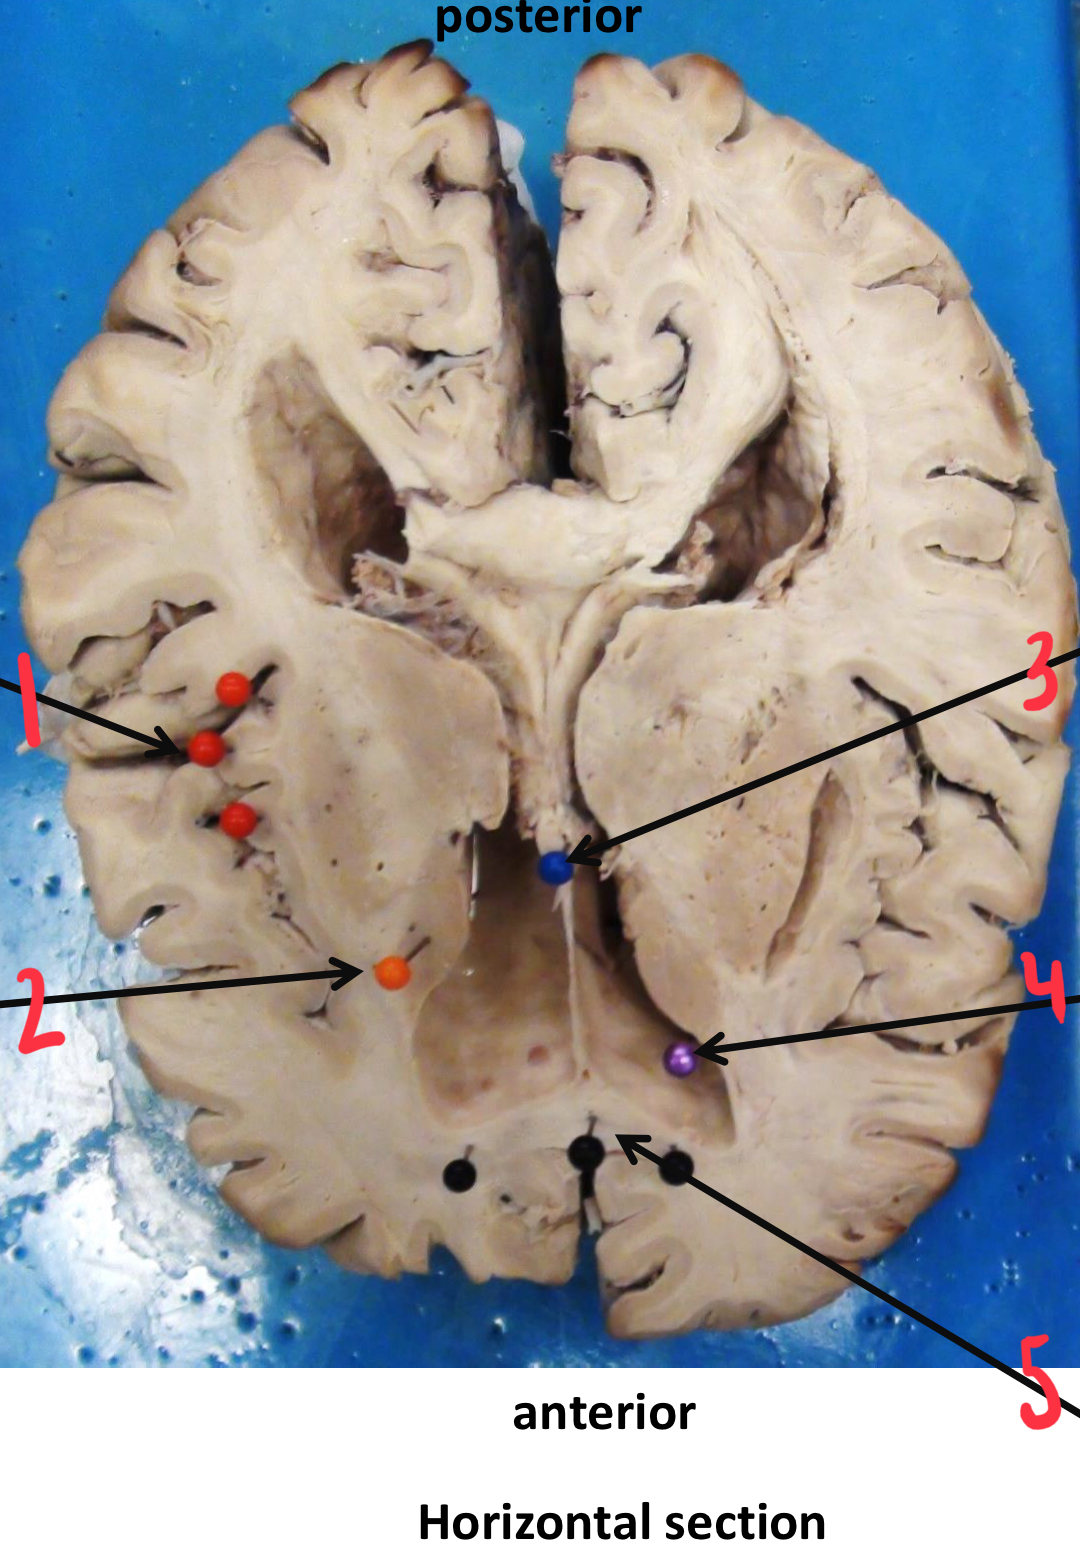

1

putamen

2

hippocampus

3

thalamus

4

internal capsule